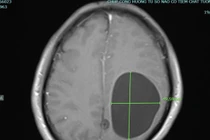

Người bệnh Hà Văn K (60 tuổi), tại huyện Thanh Sơn thường xuyên ăn tiết canh, rau sống… Khi bị đau đầu, liệt nửa người phải nhập viện thì được chẩn đoán mắc đa nang kén sán não.

Nhiễm giun sán là bệnh lý thường gặp nhất do ăn rau sống không được rửa sạch sẽ với tỷ lệ từ 5 - 7%. Người bệnh nhiễm giun sán có thể bị động kinh, liệt tay chân, rối loạn trí nhớ nếu không được điều trị kịp thời.